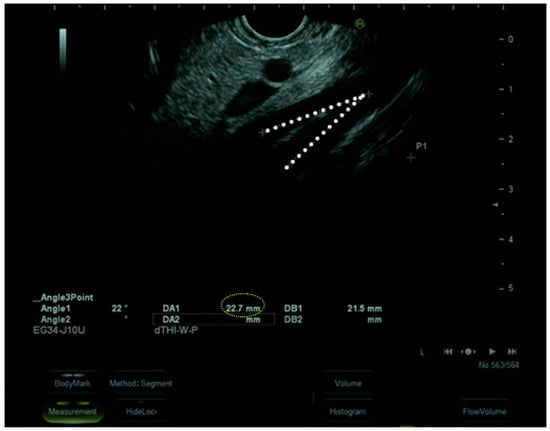

| Case index | Acute | Weight loss, Vomiting | 5 months | Upper gastrointestinal endoscopy | ||||